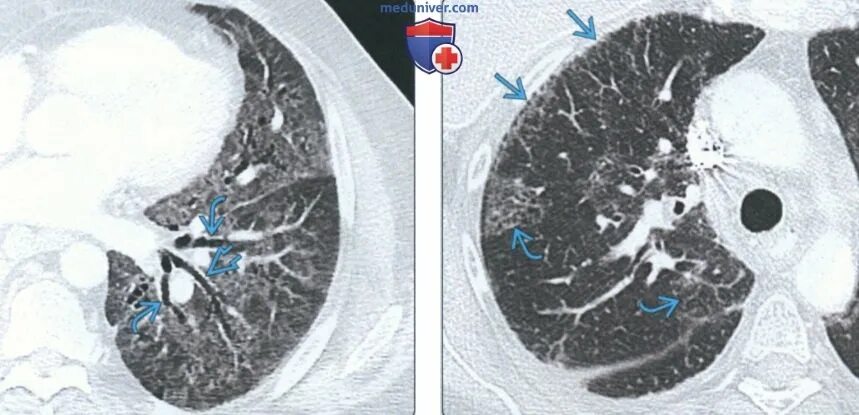

Уплотнения паренхимы по типу матового стекла